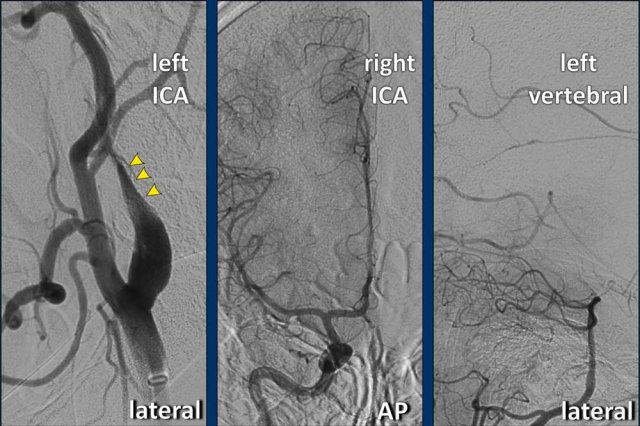

The CTA of the neck shows the typical flame shape of the proximal ICA indicating a dissection.

Continue with the axial slices...

The axial image shows a dilated left ICA with an eccentric compressed lumen.

In conclusion there is a 35-year old women with a massive stroke (NIHSS = 27), a carotid occlusion as a result of a dissection, but no intracranial occlusion.

The DSA of the left ICA confirmed the dissection (arrowheads) by demonstrating the flame shaped configuration of the proximal ICA .

Subsequently a DSA of the right ICA

and the left vertebral artery was performed.

The angiography of the right ICA showed

an absent Acom as not contrast crossed from right to left. In addition,

contrast injection in the left vertebral artery showed an absence of a Pcom.

This was proof of the diagnosis "Isolated carotid artery".